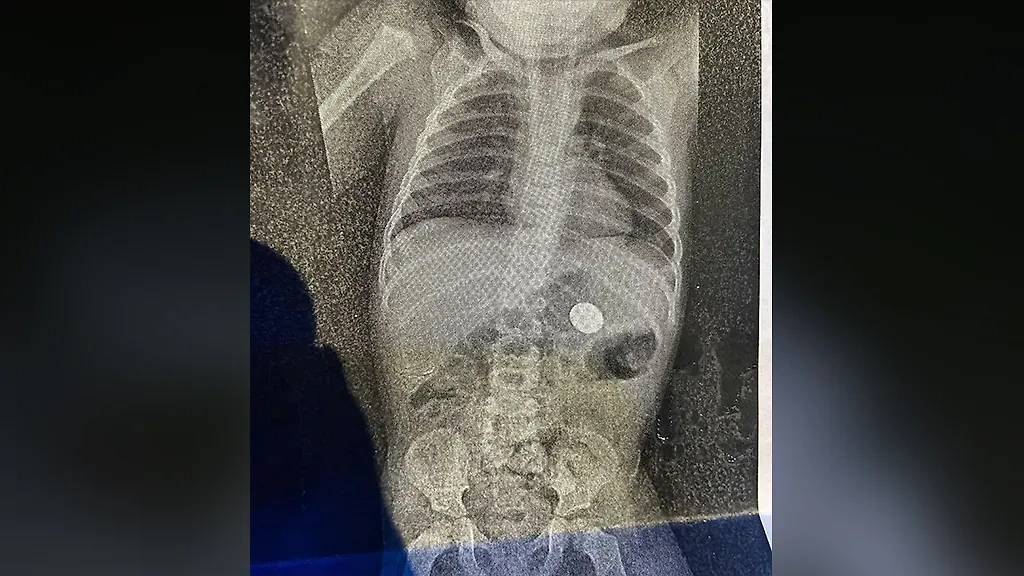

"На День святого Валентина мой сын решил показать мне свой первый фокус: исчезновение монетки. Один рентген позже — я её нашла", — Ordinary-Possession4.

Фото © Reddit / Ordinary-Possession4